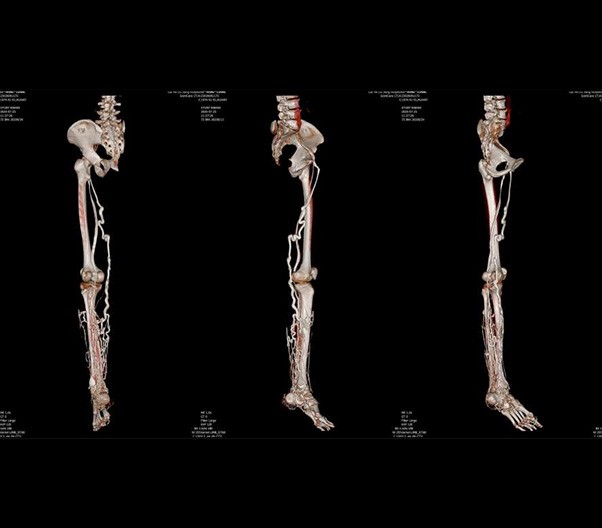

臨床畫廊